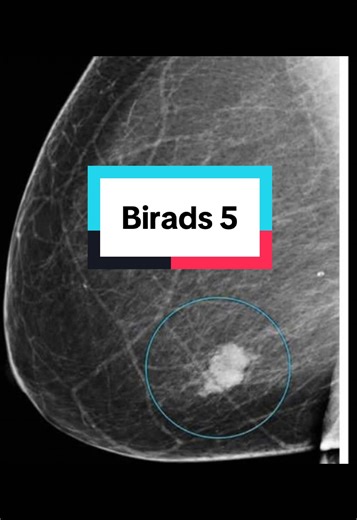

BI-RADS 5 means the radiologist sees a finding on breast imaging t

…

9.9K views

3 weeks ago

TikTok

theultrasoundlady